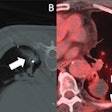

| Images of a malignant gastric ulcer in a 65-year-old man. VG image (above) shows en face view of ulcer, and endoscopic image (below) shows minimal oblique view of ulcer at the gastric part of the body with uneven ulcer base, irregular ulcer shape, irregular ulcer margin, and associated gastric folds with rugae interruption (arrows). Images republished with permission from RSNA: Chen C, Kuo Y, Lee C, et al. Differentiation between malignant and benign gastric ulcers: CT virtual gastroscopy versus optical gastroendoscopy. Radiology. Online June 1, 2009. |

Though the techniques yielded similar results, their strengths were showcased in different types of cases. Endoscopy was more sensitive in depicting malignancy according to ulcer base, with a sensitivity of 85.5%, or 65 of 76 patients, versus VG's sensitivity of 68.4%, or 52 of 76 patients (p = 0.034). VG was more specific in depicting malignancy according to ulcer margin, with a specificity of 78.4%, or 29 of 37 patients, versus endoscopy's 63.2%, or 24 of 38 patients (p = 0.034), the authors wrote.